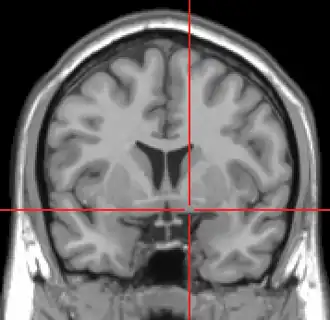

Coronal MRI slice with cross-hairs indicating location of the substantia innominata | |

The substantia innominata, also innominate substance or substantia innominata of Meynert (Latin for unnamed substance), is a series of layers in the human brain consisting partly of gray and partly of white matter, which lies below the anterior part of the thalamus and lentiform nucleus. It is included as part of the anterior perforated substance (as it appears to be perforated by many holes which are actually blood vessels). It is part of the basal forebrain structures and includes the nucleus basalis. A portion of the substantia innominata, below the globus pallidus is considered as part of the extended amygdala.[1]